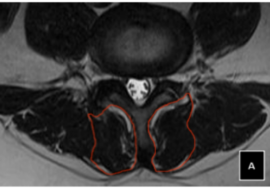

في حال ملاحظة أي من هذه العلامات، يجب استشارة الطبيب على الفور لعمل فحص سريري وتصوير بالأشعة إذا لزم الأمر.

الاعوجاج حالة مستمرة ولهذا السب قد تحتاج تدخلًا في مراحل مختلفة من العمر. وبفضل وجود تقنيات التصنيف المعتمدة ، يمكن للأطباء تصميم خطة علاجية مخصصة تضمن تدخلاً جراحيًا عند الضرورة أو العلاج غير الجراحي قبل ذلك، لتفادي الاضطراب في الوظائف التنفسية أو أي أعراض متأخرة. فريقنا المحترف يضم نخبة من الأطباء والمتخصصين الذين يجمعون بين الخبرة والاحترافية لتقديم خطة علاجية شاملة ومخصصة لحالتك، تضمن السيطرة على الانحناء ومنع زيادته.